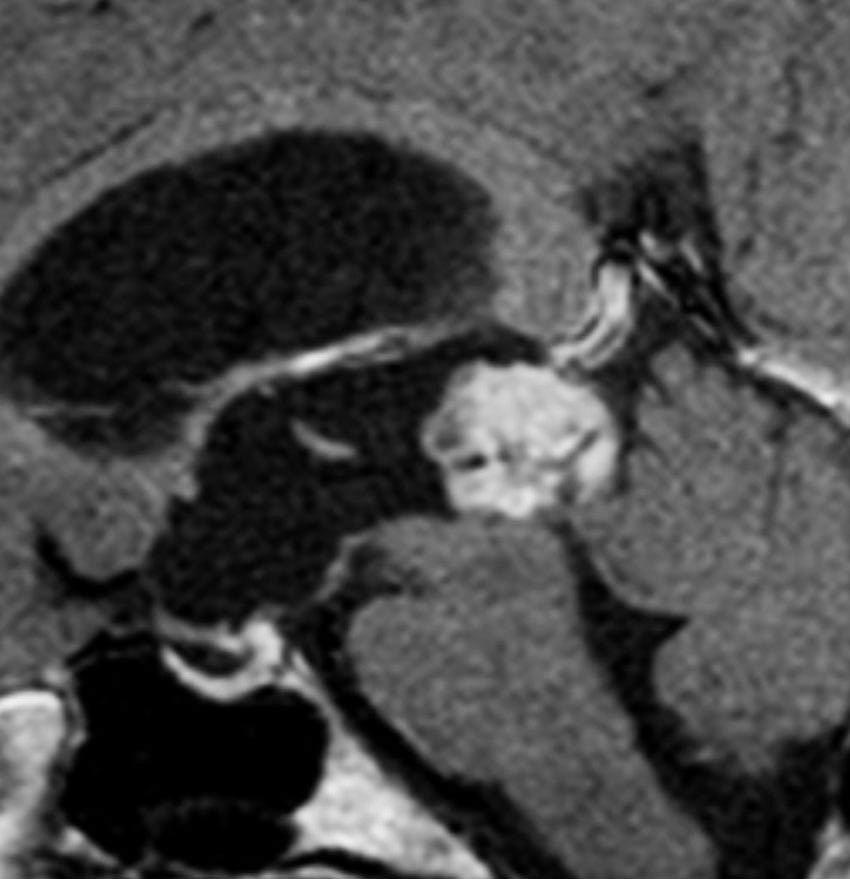

放射線化学療法後の画像です。腫瘍境界は不明瞭(左)で,腫瘍内出血(中央)して,左の視床に浸潤しています。かなりリスクは高いのですが,これを開頭手術で全摘出しました(右),この時点で完全寛解 CR です。この後にさらに化学療法と幹細胞移植(PBSCT,大量化学療法)が加えられました。